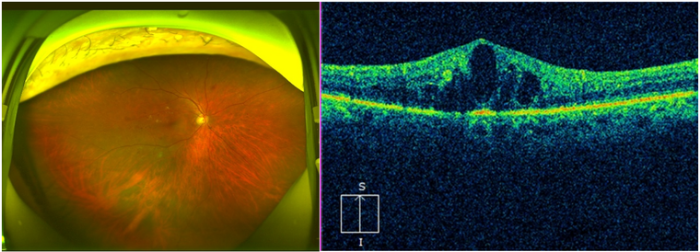

图:患者眼底检查显示视网膜散在微血管瘤,点片状出血渗出、黄斑区水肿明显

52岁的张叔叔(化名)患2型糖尿病10年,长期未规律监测血糖及眼底。日前因右眼突发视物模糊、视野中央出现扭曲变形就诊。经昆明艾维眼科医院眼底病科何雨檀主任检查发现,右眼视网膜散在微血管瘤,点片状出血渗出,黄斑区水肿明显,光学相干断层扫描(OCT)证实黄斑中心凹厚度达450μm,确诊为非增殖期糖尿病视网膜病变(NPDR)伴黄斑水肿(DME)。

“长期高血糖导致视网膜微血管渗漏和缺血,黄斑水肿是视力下降的主因。患者右眼视网膜大量出血,黄斑区严重水肿,视力仅剩0.1,若再延误可能导致永久失明。”何主任迅速制定 “抗VEGF药物+激光+血糖管控”联合方案。经3个月治疗,张先生双眼病情稳定,黄斑水肿消退,视力提升至0.5,生活自理能力显著恢复。